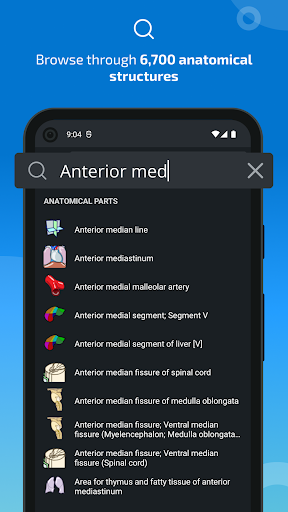

* اعثر على الأجزاء التشريحية الخاصة بك بسهولة أكبر بفضل ميزة البحث الجديدة والأكثر سهولة وقوة

* تحسين أداء البحث عن البنية التشريحية